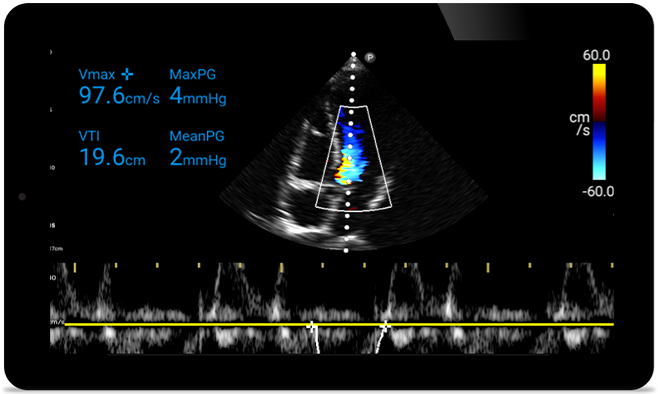

Act faster to protect their heart

When seconds count, portable ultrasound can make the difference. Lumify can provide the high-definition imagery you need whenever and wherever you need it.

Opportunity to potentially reverse cardiomyopathy

Intro to transthoracic echocardiography